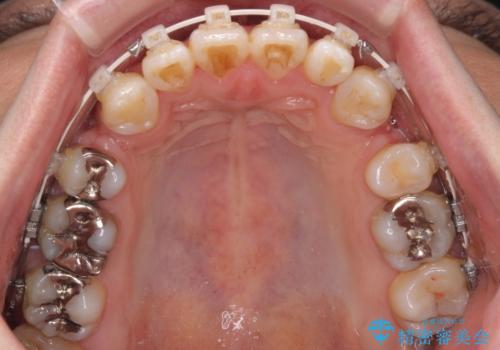

装置は、透明感のあるクリアブラケットとホワイトコーティングされたワイヤーを使用した、目立ちにくい審美装置を選択。

治療期間は約2年。

少しずつ前歯を後ろに下げていくことで、横顔のラインが整い、口元の“出っ張り感”が解消。

治療後には「自然に笑えるようになった」と嬉しいお声をいただきました。